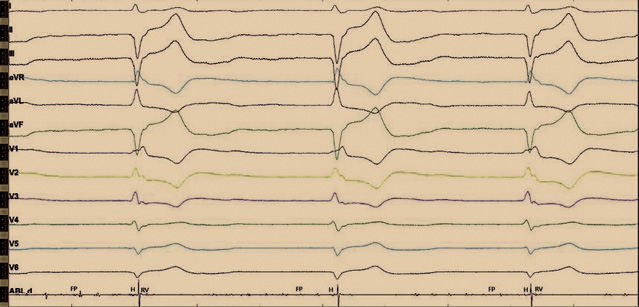

При эхокардиографии после операции незначительно увеличилась фракция выброса (53%). Сократительная способность миокарда левого желудочка сохранена. Перикардиального выпота нет. При программировании электрокардиостимулятора на следующие сутки нарушений функции детекции и стимуляции не выявлено (рис. 4). ЭКС работал в режиме DDD(R) с базовой частотой 60 ударов в минуту. Импеданс желудочкового электрода составлял 551 Ом, гисиального электрода – 464 Ом. Чувствительность желудочкового электрода была 8,5 мВ, гисиального электрода – 0,9 мВ. Порог стимуляции: хронический по желудочковому каналу – 0,7 В, гисиального электрода – 5,5 В при длительности импульса 1,5 мс. Амплитуда стимуляции была запрограммирована на 6,5 В при длительности импульса 1,5 мс, срок службы ЭКС – менее 5 лет. Учитывая малый срок службы ЭКС Medtronic Adapta и высокие параметры стимуляции, пациенту рекомендовано повторное программирование через 1 месяц.

Рис. 4. Электрокардиограмма после операции. Отражена постоянная желудочковая стимуляция после имплантации гисиального электрода. Стимуляционный комплекс не расширен, соответствует нативному. Определяются стимуляционный спайк, изолиния и сокращение желудочков. Имеется также второй страхующий стимул, после которого нет ответа, по типу псевдосливного комплекса. Изолиния отражает замедление проведения по специализированным клеткам проводящей системы, с последующим сокращением по системе Гиса – Пуркинье. Длительность QRS составляет 110 мс